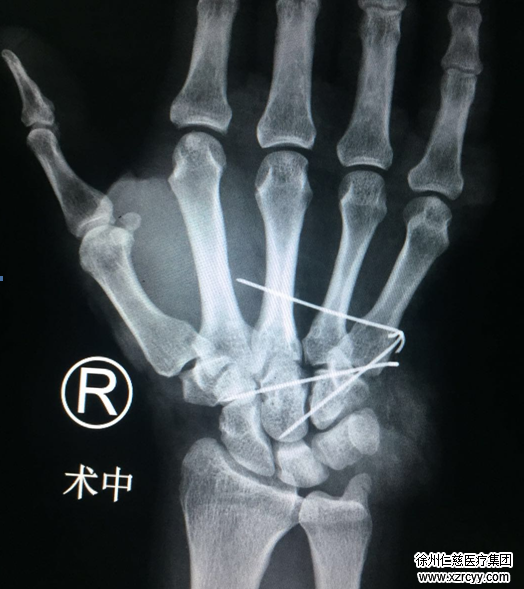

患者儿子即刻驱车带老人来到betway在线登陆,在手外科二病区齐伟亚科主任及唐洪伟医疗小组的努力下,经过4个小时的手术,给予患者骨折、脱位复位内固定,断裂的血管、神经、肌腱逐一修复,目前患者生命体征平稳,右手各指活动良好,各指色红润,毛细血管反应灵敏,送入病房进一步观察病情和康复。